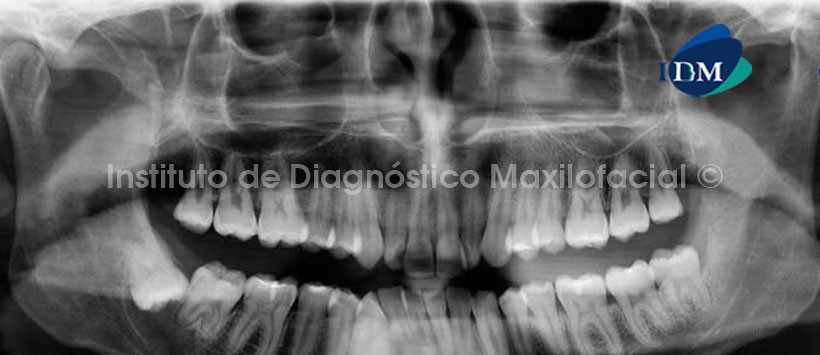

En la radiografía panorámica (Fig 1) se observa una imagen radiolúcida unilocular de limites definidos y corticalizados, asociada a la corona de la pieza 4.8 sugerente de Quiste Dentígero.

Al estudio con tomografía volumétrica, en el corte tangencial (Fig. 2) confirmamos la formación quística envolviendo la corona de la pieza 4.8, condicionando la posición invertida de esta, con las raíces próximas al borde anterior de la rama ascendente. En el corte axial (Fig. 3) se observa el proceso osteolítico en contacto con la raíz distal de la pieza 4.7, así como el adelgazamiento de la tabla ósea lingual. En el corte transaxial (Fig. 4) se observa el origen de la lesión a nivel de la unión cemento-adamantina (UCA) de la pieza 4.8 y el desplazamiento basal del conducto dentario inferior.